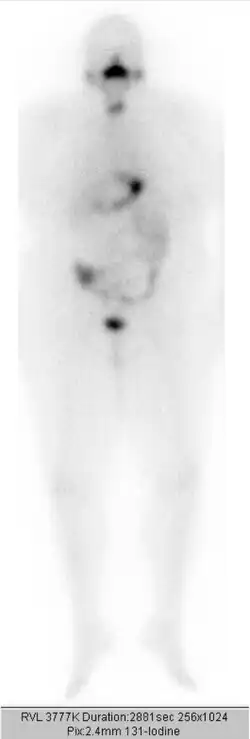

Einige Tage nach der Therapie wird ein Ganzkörperszintigramm angefertigt. Die Therapie wird in etwa dreimonatigen Abständen wiederholt, bis weder das Szintigramm, das Ultraschallbild der Halsregion, noch der Tumormarker Thyreoglobulin einen Hinweis auf nennenswertes verbliebenes Schilddrüsengewebe (gutartig oder bösartig) geben. Eine Gesamt-Aktivität über alle durchgeführten Radiojodbehandlungen von bis zu 74 GBq (2000 mCi) wird bei sonst gesunden Patienten meist problemlos vertragen. Bei höherliegenden Aktivitäten ist mit einem erhöhten Risiko für eine dauerhafte Schädigung des Knochenmarks als blutbildendes Organ zu rechnen.

Der Ablauf – mit Jodkarenz, Stimulation des TSH mit anschließender Bestimmung des Tumormarkers Thyreoglobulin und oraler Gabe des Jods sowie der Durchführung der Ganzkörperszintigrafie – entspricht dem Ablauf bei der ablativen Therapie. Unterschiedlich ist dagegen die Höhe der verabreichten Aktivität, üblich sind etwa 100 bis 400 MBq Jod-131 oder 40 bis 200 MBq Jod-123.